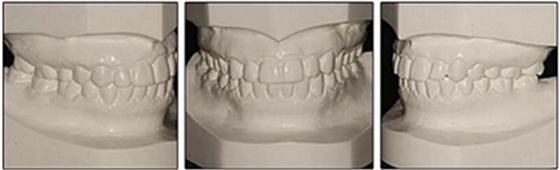

患者決定采用非手術(shù)治療方法,側(cè)貌沒(méi)有任何預(yù)期的變化。治療后面部照片(圖5)顯示她改善的微笑和側(cè)貌,包括尖牙保護(hù)合。由于先天性第一前磨牙缺失,右磨牙關(guān)系為III類。治療后牙齒石膏模型(圖6)顯示實(shí)體牙齒交錯(cuò)排列情況,并且全景X線片顯示可接受的牙根平行度而且沒(méi)有牙根吸收表現(xiàn)(圖7)。最終的頭影測(cè)量片(圖7)證實(shí)了面部評(píng)估,并且描跡圖顯示深覆蓋的改善,同時(shí)保持上頜切牙位置并通過(guò)測(cè)量ANB角度和Wits評(píng)估改善骨性II級(jí)關(guān)系(表)。治療前后的疊加圖顯示由于下頜切牙前傾的增加改善了下唇平衡(圖8)。如相關(guān)治療計(jì)劃所預(yù)測(cè)的那樣,B點(diǎn)出現(xiàn)。A進(jìn)行牙科錐形束計(jì)算機(jī)斷層掃描以記錄下頜前牙區(qū)的骨質(zhì)變化。如預(yù)期的那樣,由于治療導(dǎo)致該區(qū)域的骨量增加(圖9)。

放置上頜和下頜尖牙到尖牙的聯(lián)合保持器,并使用支持性上頜環(huán)繞Hawley保持器進(jìn)行夜間佩戴以加速關(guān)閉所有帶狀間隙。

最終評(píng)估結(jié)果如下:(1)美觀改善; (2)達(dá)到了生理功能; (3)患者對(duì)治療結(jié)果完全滿意; (4)上頜尖牙的角度和下頜切牙的傾斜度有所改善(表); (5)形成了穩(wěn)定的牙周終點(diǎn),并觀察到附著齦的厚度改善; (6)病人會(huì)從下頜前移中受益,但她不想改變她的側(cè)貌; (7)長(zhǎng)期變化(6年)是穩(wěn)定的,在B點(diǎn)再生的骨保持穩(wěn)定,咬合關(guān)系得到改善(圖10和11;表)。